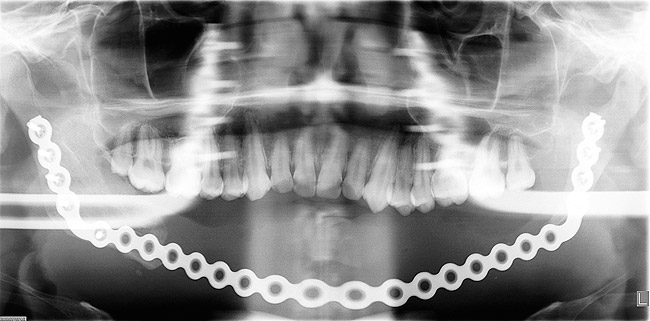

Mandibular reconstruction occurred in June 2007. All remaining lower teeth were removed, and a subtotal mandibular resection was performed to remove the ameloblastoma, which extended from slightly below the left mandibular condyle to the right angle of the mandible (Figure 5). The tumor was removed intact; it measured 10.2 cm x 7.4 cm x 7.1 cm. Mandibular reconstruction can be challenging for the surgeon wishing to restore its unique geometry; however, reconstruction can be achieved with titanium bone plates followed by autogenous bone grafting. In this case, incorporation of the bone graft into the mandible provided continuity and strength required for primary esthetics and function and permitted dental implant rehabilitation at a later stage.

Figure 5  Panoramic radiograph shows a titanium reconstruction plate in place after tumor resection from left subcondylar region to the right angle of the mandible.

Figure 5